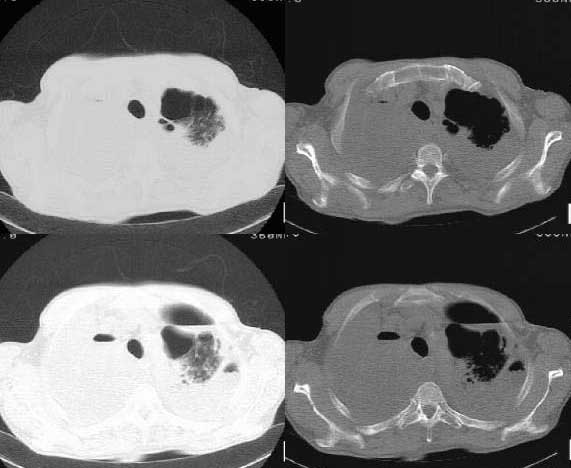

以下是引用woaixct在2006-6-23 12:15:00的发言:[br]第一张胸片示:右肺上叶为大片致密影占据,左肺上见大片致影及空洞性病灶并有液平;[br]第二张胸片示:左肺上叶致密影及空洞性病灶基本吸收,而右肺上叶之病灶有少许吸收改变;[br]ct片示:右上叶大片软组织密度,右肺门区至右肺上叶见巨大软组织块,内见支气管充气征,上纵隔右移,主气管及上叶支气受压变扁,中间支气管狭窄,左肺上叶空洞性病灶并有液平,左肺上叶尖后段见大片致密影,结合2张胸片考虑,ct片是4月份所摄,而不是6月份的片子;[br]结合2张胸片及ct片考虑:[br] 1.右中央型肺癌伴右肺上叶不张;[br] 2.左肺上叶尖后段炎性变及左肺脓肿;[br]第2张胸片提示:经过一个多月的不规则抗炎治疗,左肺上叶病灶及右肺上叶不张病灶基本吸收,而右肺占位无明显变化。

以下是引用jiangjing在2006-6-23 21:21:00的发言:[br]个人考虑还是两肺感染性病变可能大,主支气管及叶支气管是通畅的,并可见支气管气相;ct提示病变是以肺叶分布的,密度相对均匀;胸片可见有叶间裂下坠征,是不是考虑克雷伯杆菌感染可能.病人前后两张片比较病变是增多[应该考虑混合感染可能性大,右肺癌待排建议查痰及穿刺检查]